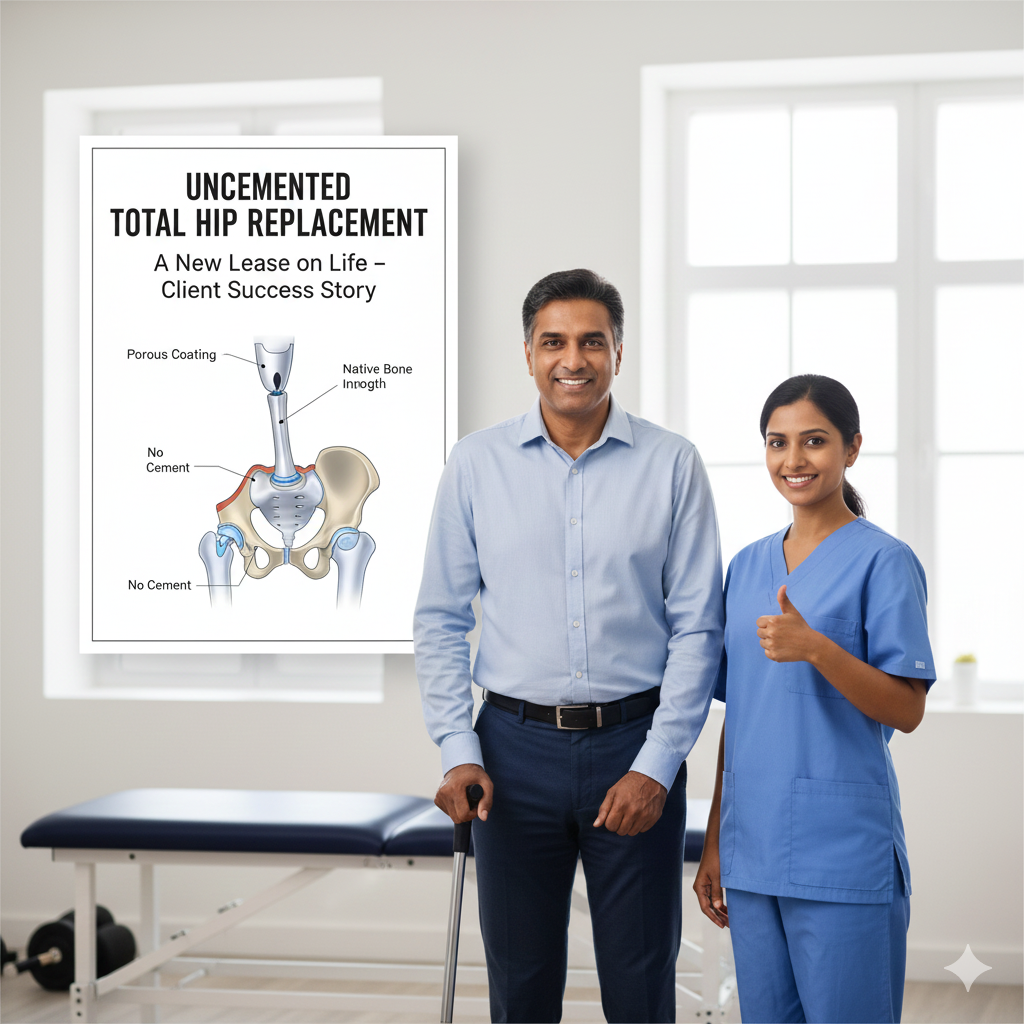

An Uncemented Total Hip Replacement (THR), also known as biological fixation, is a sophisticated surgical technique utilized to replace a damaged hip joint without the use of bone cement (Polymethyl methacrylate or PMMA). This procedure is increasingly favored for younger, more active patients with good bone quality.In an uncemented THR, the fixation relies entirely on the body’s natural healing process: osseointegration.